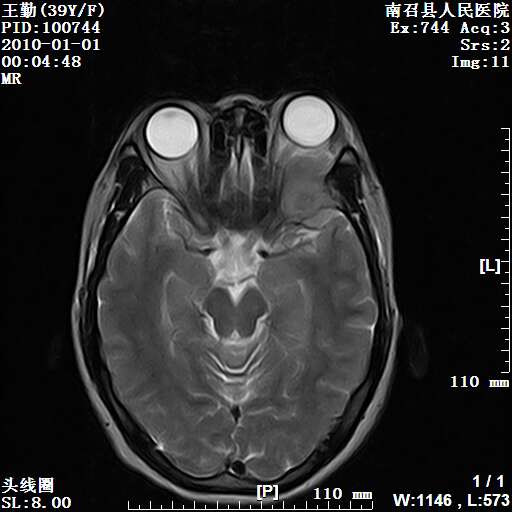

以下是引用随光逐影在2010-1-22 9:03:00的发言:[br]考虑左侧中颅窝(蝶骨翼区)脑膜瘤侵犯蝶骨翼并突入左侧眼眶。

以下是引用水过无痕在2010-1-22 14:55:00的发言:[br]一、定位:颅外占位;二、定性:恶性可能性大;三、组织来源:来源于左侧眼外直肌或其他部位;考虑为:横纹肌肉瘤>转移瘤>脑膜瘤.